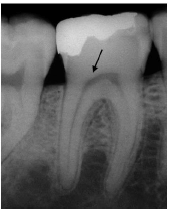

A polpa reage de maneiras diferentes à presença de agentes ou estímulos agressores, e seus principais mecanismos de defesa são: redução da permeabilidade dentinária, formação de dentina terciária e desenvolvimento de uma resposta imune. A partir dos seus conhecimentos sobre radiologia e respostas da polpa à agressão, analise a imagem abaixo e assinale a alternativa que apresenta a descrição correta da representação: